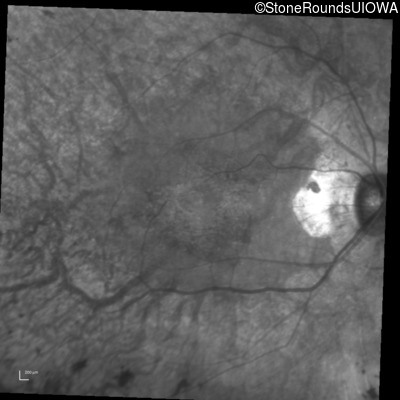

Infrared Fundus Photograph - Right - 20/20

Exemplar